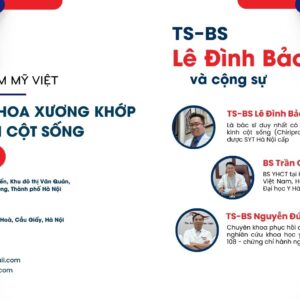

- Đội ngũ bác sĩ